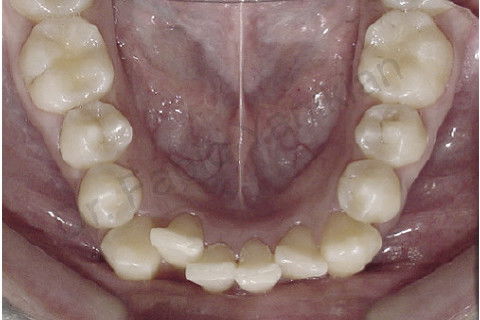

Foto oclusal superior inicial

Foto oclusal inferior inicial

Paciente CL I com apinhamento superior e inferior

Evolução clínica: exo dos 4 prés, alinhamento e nivelamento, não foi necessario fazer RAS e RAI mas perda de ancoragem nos 4 quadrantes para fecar os espaços.